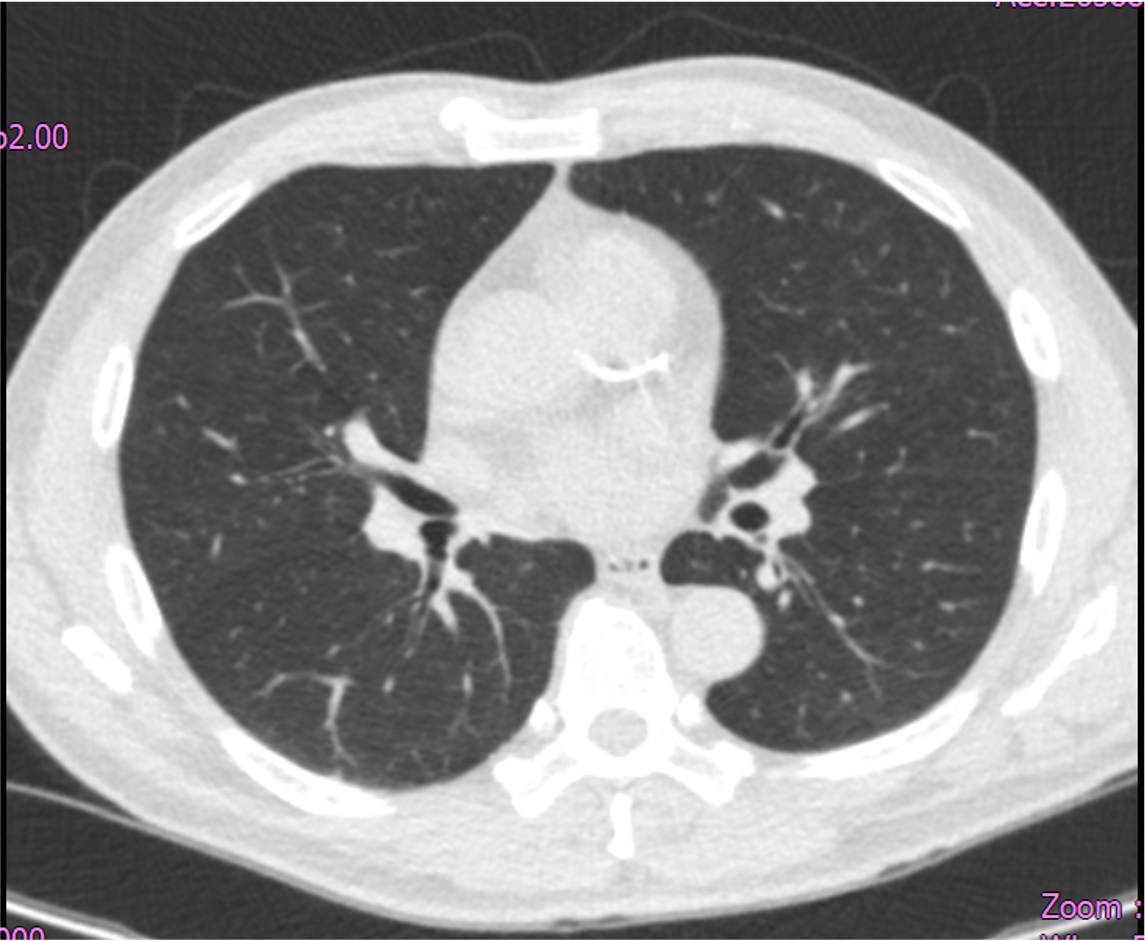

A 65-year-old man with hypertension, dyslipidemia, hyperuricemia, and CKD stage 3 presents with unstable angina. He had a positive treadmill test three years ago but deferred angiography. Recent LDCT for cough survey disclosed a coronary calcified lesion. He reports smoking 2 PPD, with no family history of cardiovascular disease. Physical examination shows normal heart sounds with no murmurs and no signs of heart failure.

Relevant Test Results Prior to Catheterization

Echocardiography showed adequate systolic and diastolic function, with no reginal wall motion abnormality detected. Thallium study showed moderate stress induced ischemia involving the inferior and basal inferoseptal segments, and mild ischemia involving the apex, mid anterior, and basal anteroseptal segments, indicating multi-territory inducible ischemia.